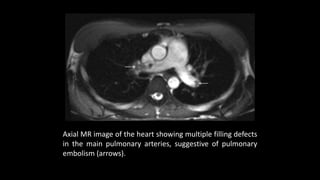

Axial MR image of the heart showing multiple filling defects

in the main pulmonary arteries, suggestive of pulmonary

embolism (arrows).

Axial MR imageof the heart showing multiple filling defects in the main pulmonary arteries, suggestive of pulmonary embolism (arrows).